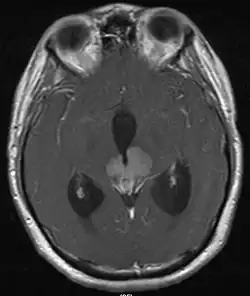

In weit über 80 % befindet sich der Tumor in der Mittellinie im Bereich der Pinealis, allerdings können bis zu 5 % der Tumore multifokal auftreten.[2] Die Diagnose wird meistens durch eine Biopsie gestellt. Auch die Bestimmung von beta-HCG und AFP im Liquor cerebrospinalis ist wegweisend.